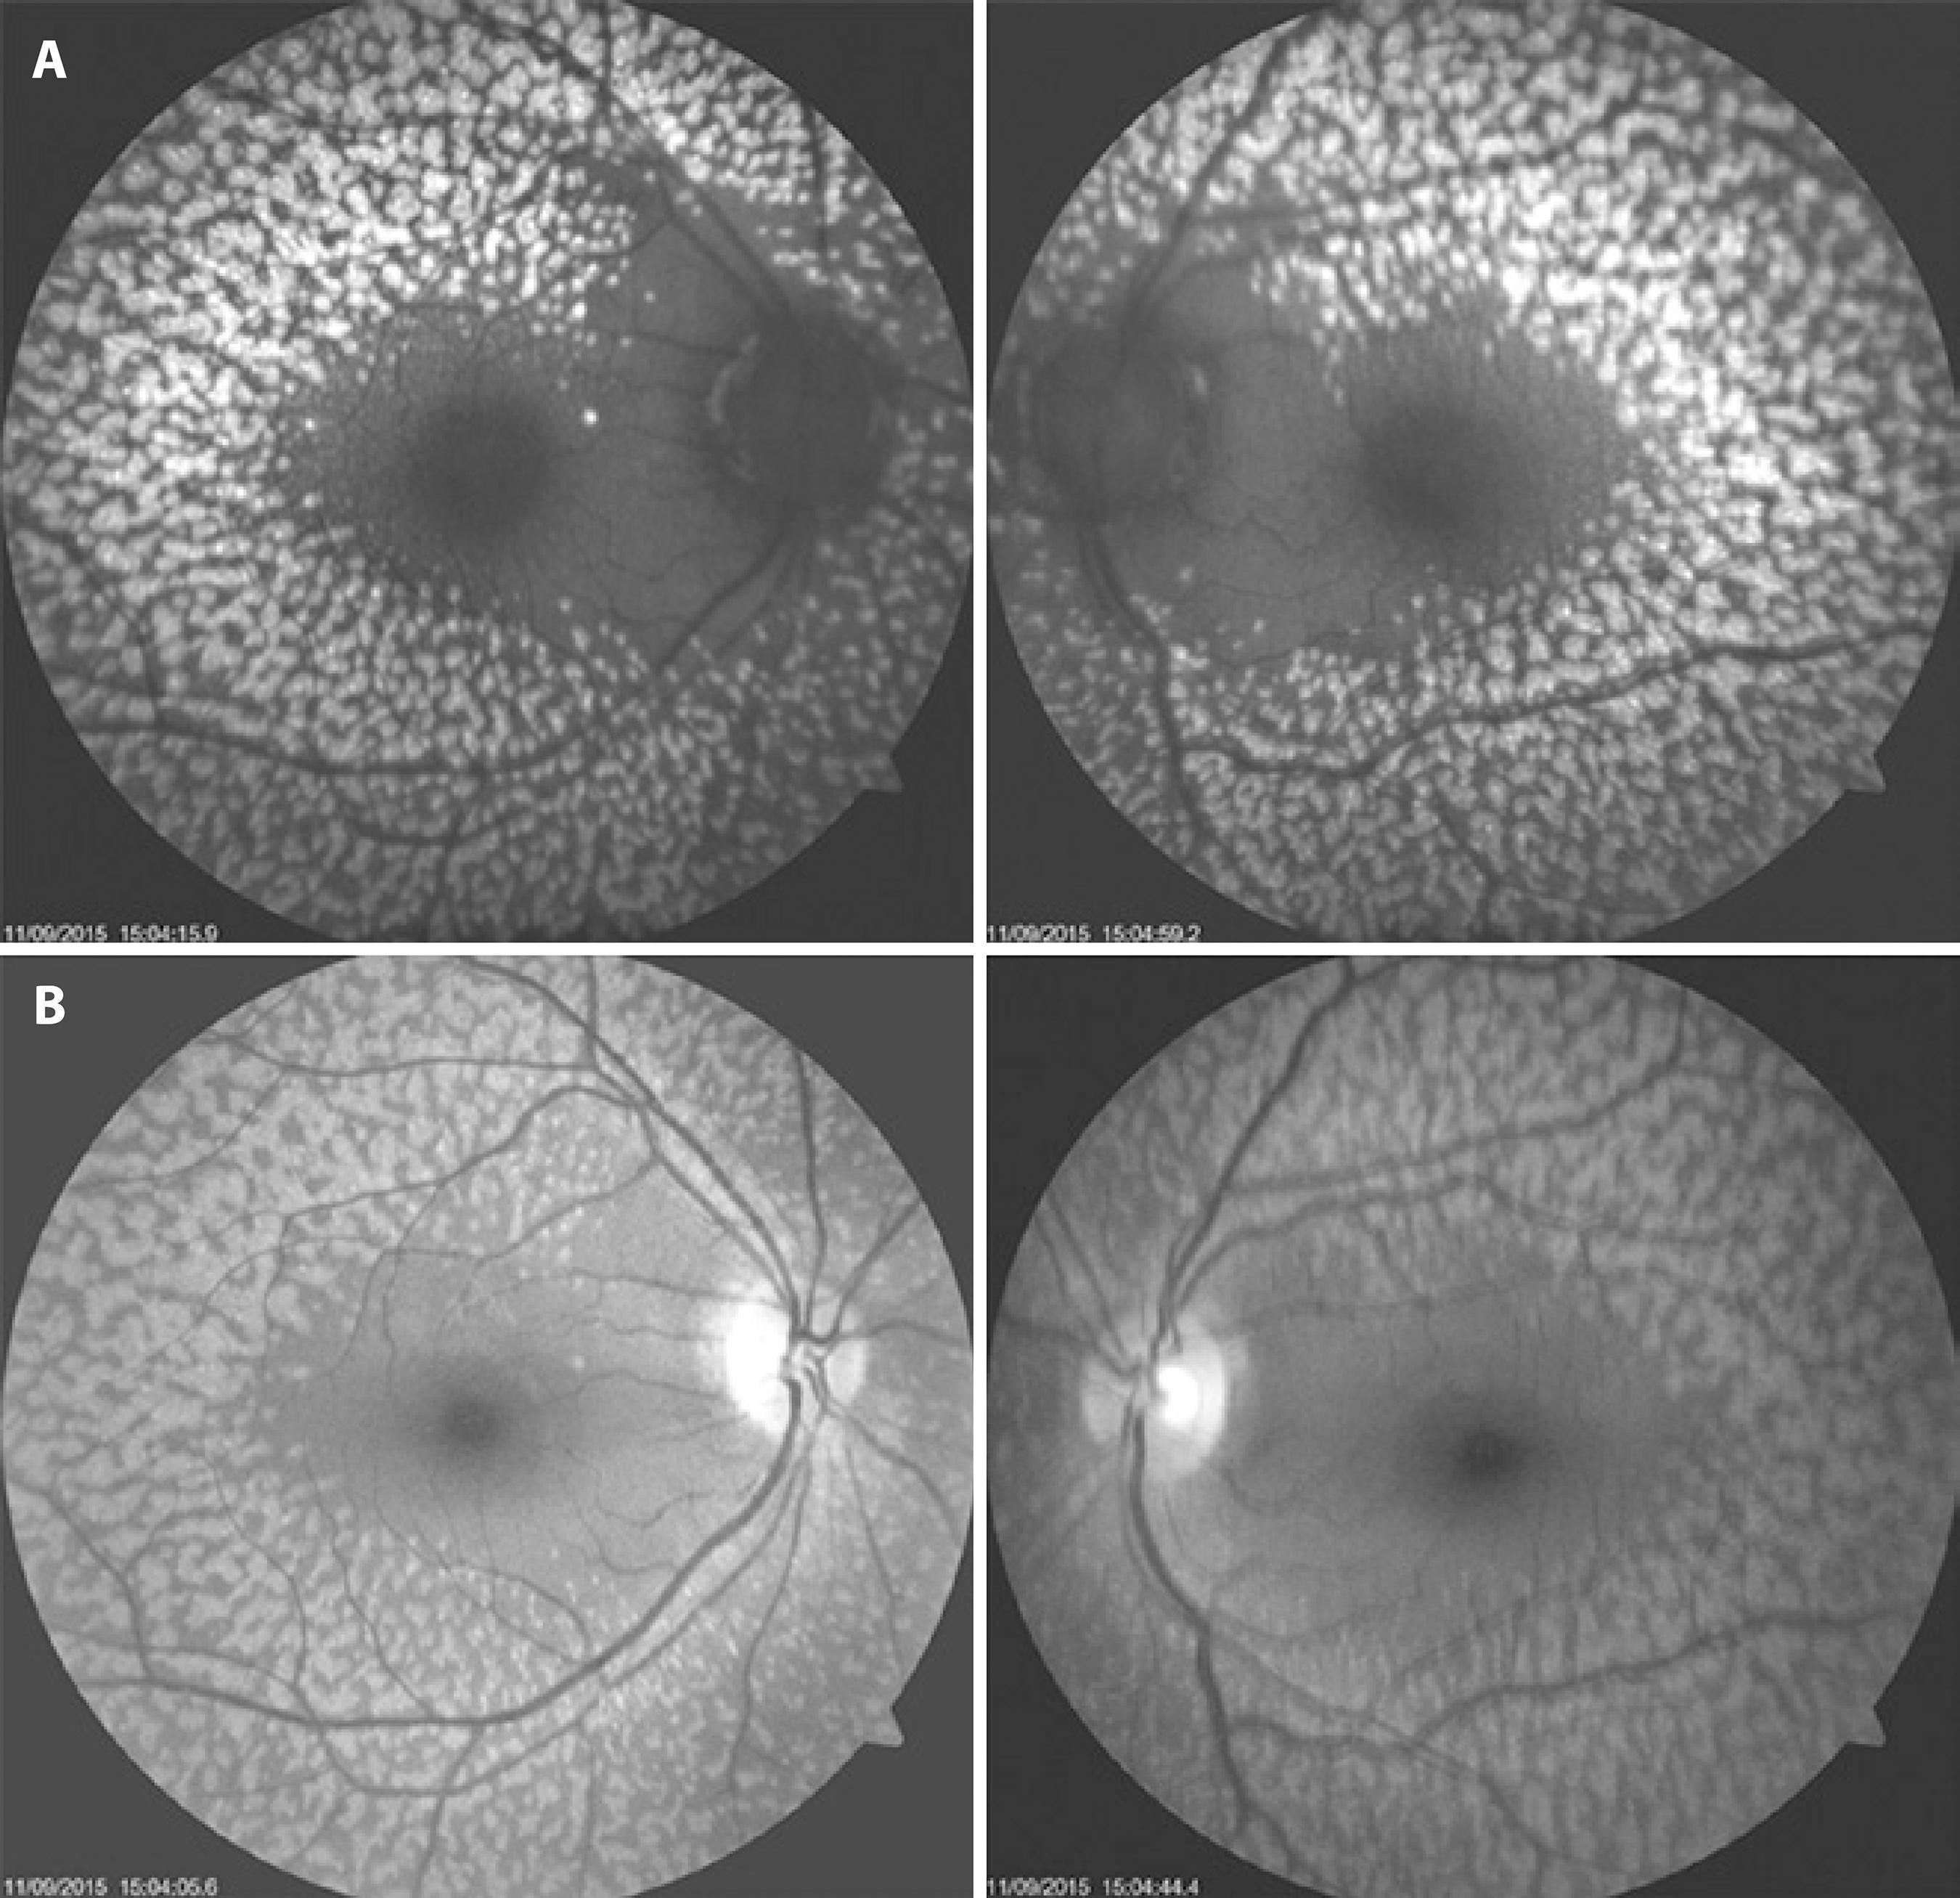

Increased autofluorescence corresponding to retinal flecks was observed in the infrared image (Figure 2). Fluorescein angiography showed a healthy macula with hypofluorescent spots related to pigment clumps; these extended to the far periphery but without macular injury. ERGs were recorded under scotopic and photopic conditions and were normal except for the selective reduced amplitude of oscillatory potentials (Figure 3). Electrooculograms revealed light peak/dark trough ratios (Arden ratios) of 1.9 in the right eye and 2.0 in the left eye (Figure 3). The patient’s macula was tested with a spectral domain (SD) optical coherence tomography (OCT) B-scan and SD-OCT angiography, using an Avanti RTVue XR with AngioVue® software (Optovue, Inc., Fremont, CA). The imaging data were obtained using split-spectrum amplitude-decorrelation angiography software. The testing demonstrated a normal foveal structure with increased thickness of the RPE in both eyes. The 3 × 3 mm SD-OCT angiography showed no macular injury from the outer retina to the choriocapillaris slab in both eyes. Projection artifacts were removed using a default proprietary algorithm (Figure 4). At a follow-up examination 18 months later, the patient continued to have no ocular symptoms.

Figure 2 A) Fundus autofluorescence demonstrating a symmetrical pattern of yellow-white fleck lesions that affected both fundi. B) Infrared imaging showing the same configuration.